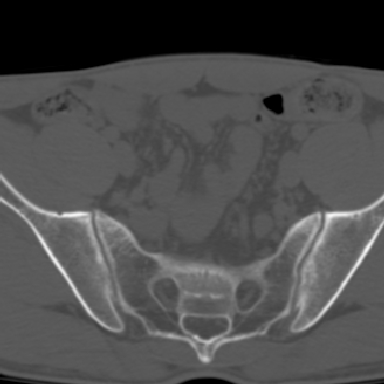

m 30 腰背部不适半年; 清晨时僵硬; 活动症状有所改善

双侧骶髂关节下2/3关节面模糊,毛糙,可见小囊状骨质破坏区.支持强直性脊柱炎.

强直性脊柱炎的早期改变!不仅表现为双侧骶髂关节,第5腰椎与骶椎间的关节突关节也有类似改变。

双侧骶髂关节下2/3关节面模糊,毛糙,髂骨侧可见小囊状骨质破坏区,骶髂关节间隙增宽(软骨破坏期)。支持早期强直性脊柱炎。

双侧骶髂关节下2/3关节面模糊、毛糙,可见小囊状骨质破坏区,呈虫咬状改变,周围可见增生硬化.支持强直性脊柱炎早期表现.

双侧骶髂关节髂骨面硬化,毛糙,小囊变,属于早期强直性脊柱炎